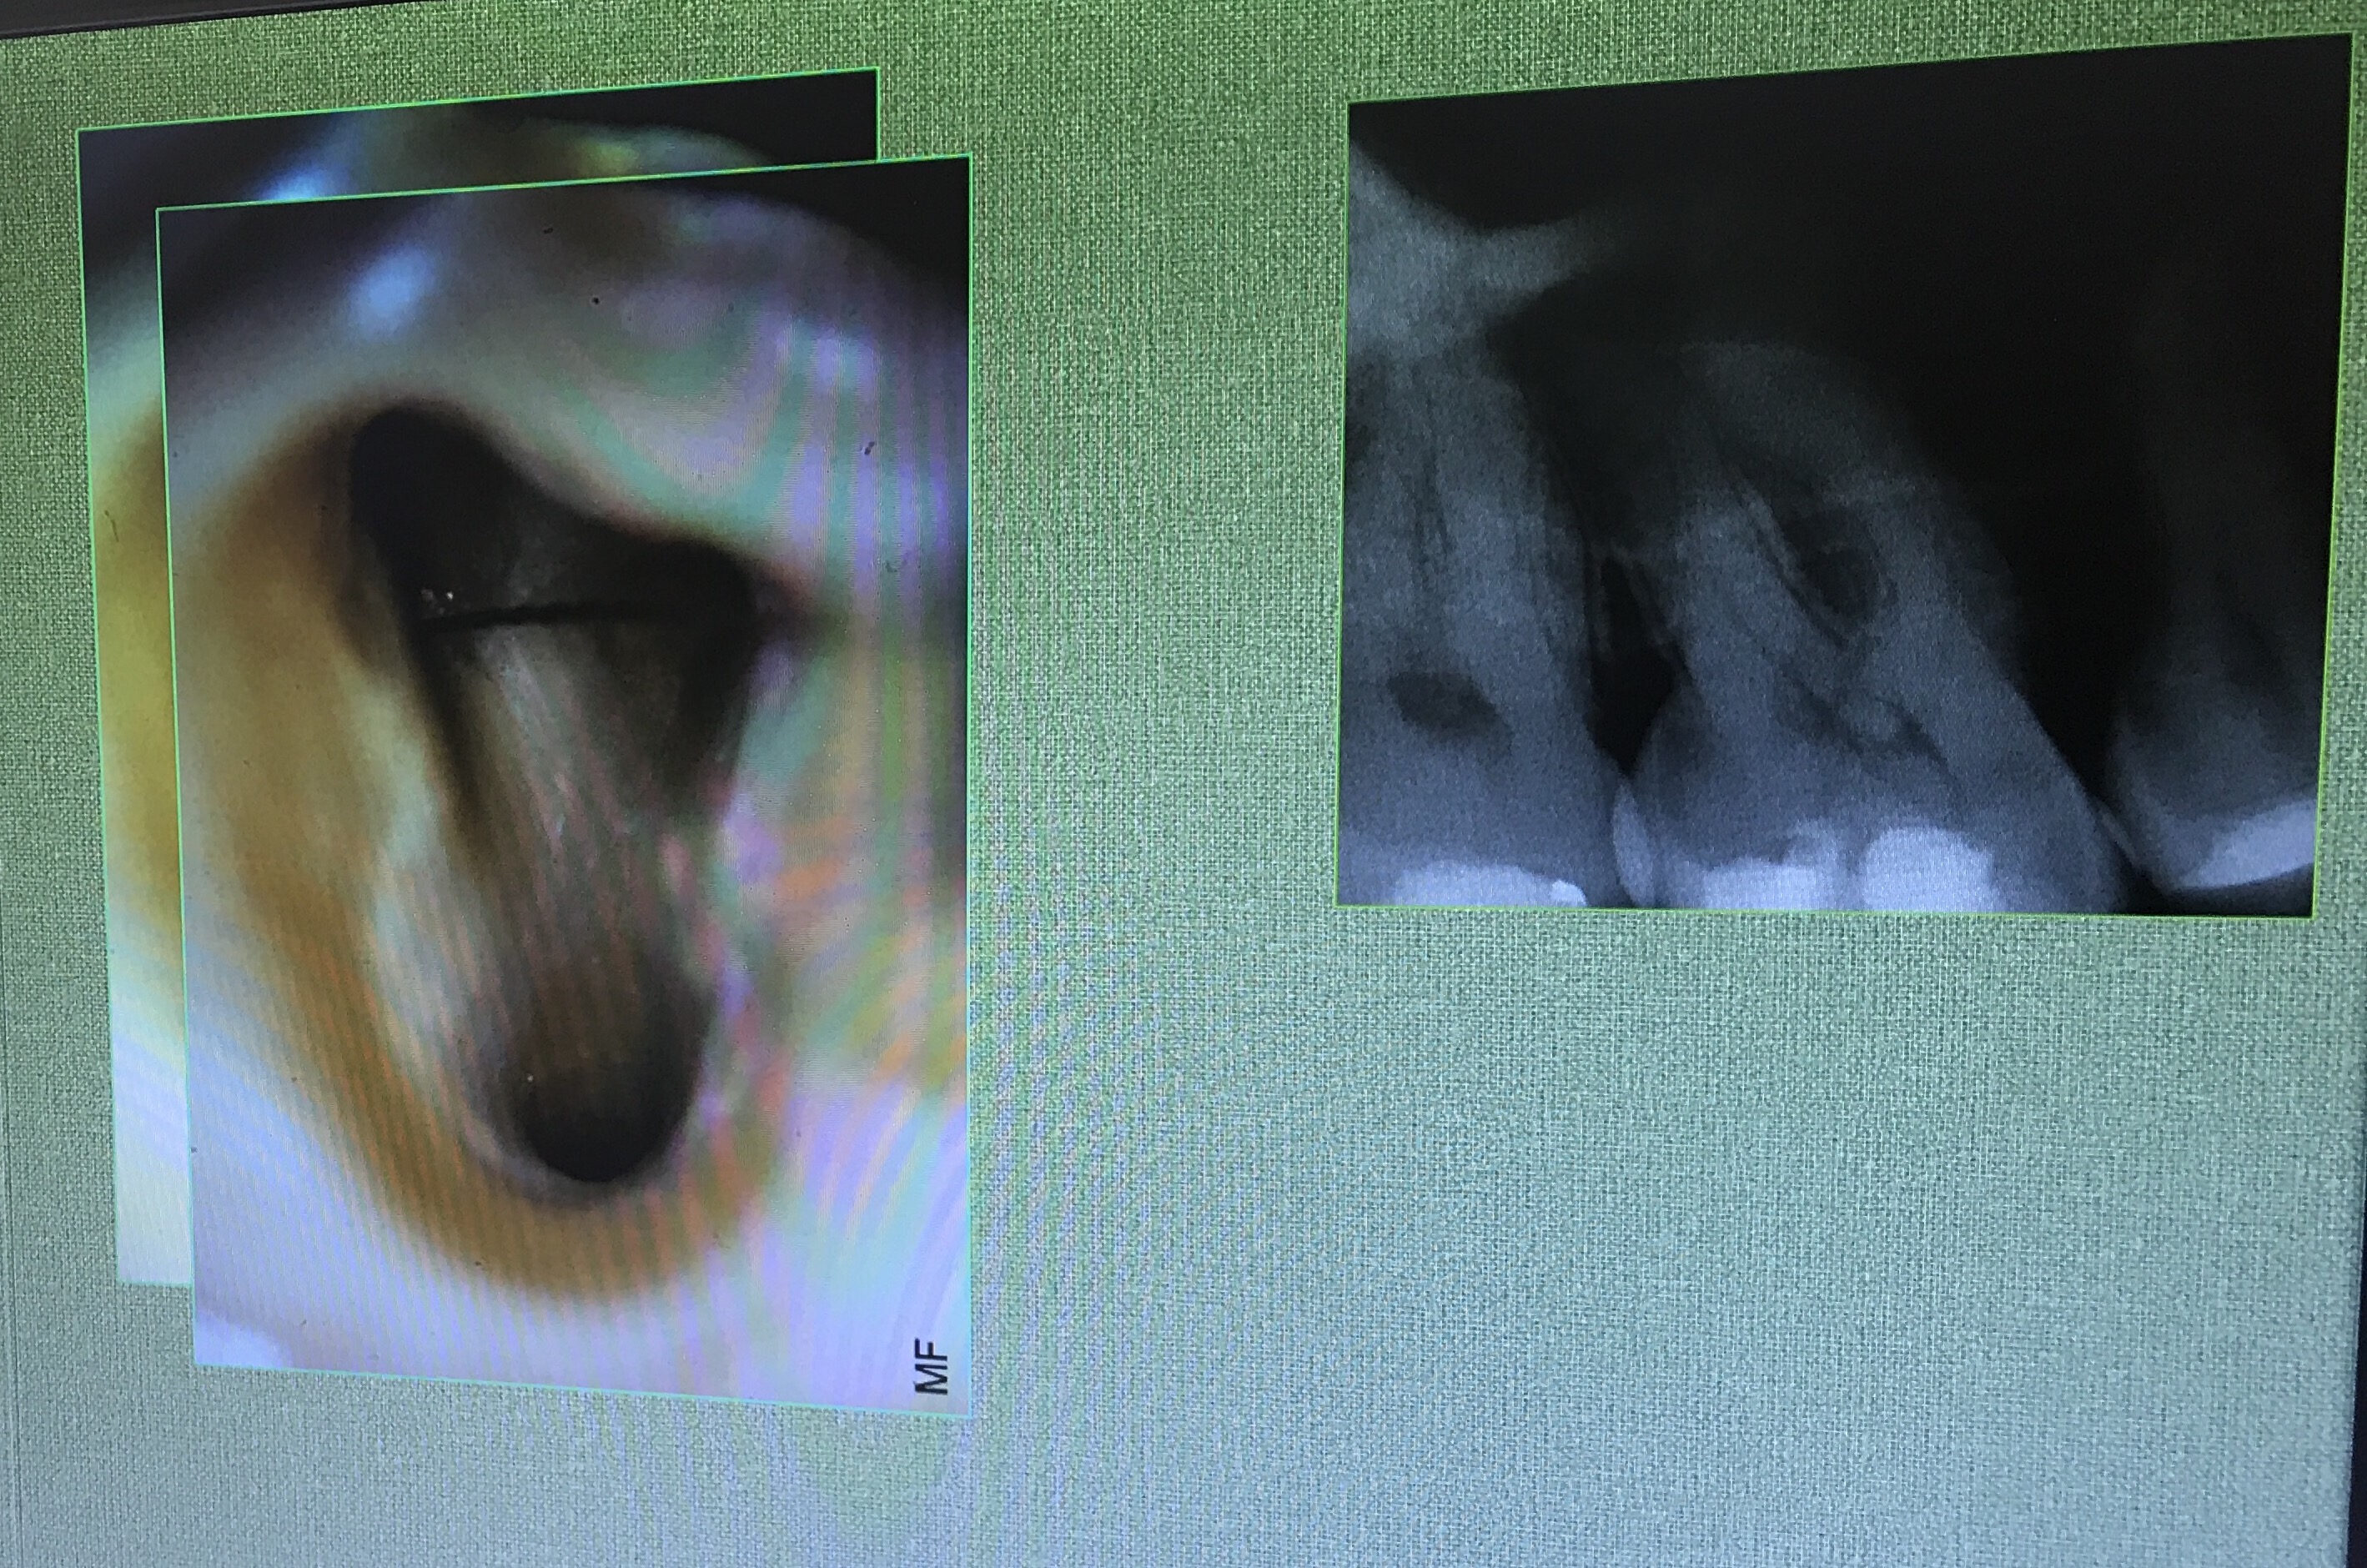

Lecture ต่อมา คือหลักการซ่อมแซม perforate

Definition

การ Dx เช่น Apex locator ร้องก่อนถึง WL , ลักษณะเหงือกบริเวณใกล้ปลายรากจะปกติ แต่บริเวณ crestal bone จะแย่ลง เป็นต้น

อันนี้คือ case จริงครับ ส่วนที่ Outline ไว้ตรงกลางคือ รอย Perforate

repair ใช้ MTA และ wet cotton (เพื่อให้ set)

อีก case

จุดสีเหลือง คือ canal ที่ถูกต้อง

วงกลมสีแดง แสดงส่วนที่ถูก repair ด้วย MTA

การ repair โดยใช้ Internal matrix

Internal matrix คือการใช้วัสดุปิดชั้นแรกสุดเข้าไปก่อน เพือป้องกันวัสดุอีกตัวที่ใช้ repair ไม่ให้รั่วไหลออกมา

วัสดุที่ใช้เป็น matrix ชั้นแรก Collaplug

เนื่องจากขนาดของมันใหญ่กว่ารอยทะลุครับ ต้องมีการตัดออกให้พอดี

หน้าที่คือ stop bleed เป็น matrix ล้อมรอบ MTA หรือ Biodentine ไว้ ไม่ให้ออกนอก canal

และวัสดุที่ใส่ลงไปเป็นชั้นที่ 2